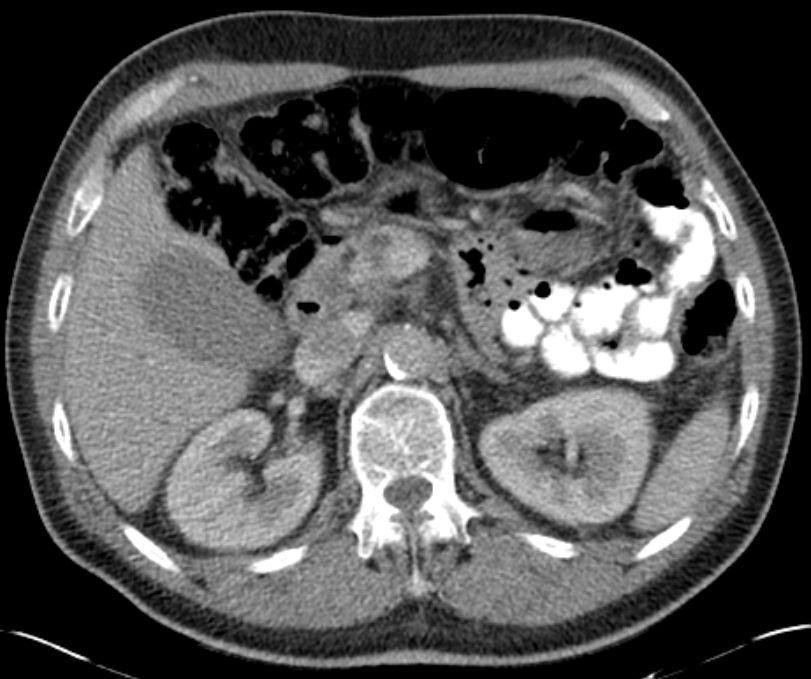

Pankreaskopfkarzinom mit Infiltration der V. mesenterica superior

|

Karzinom (roter Pfeil), V. mesenterica superior ist infiltriert (grüner Kreis)